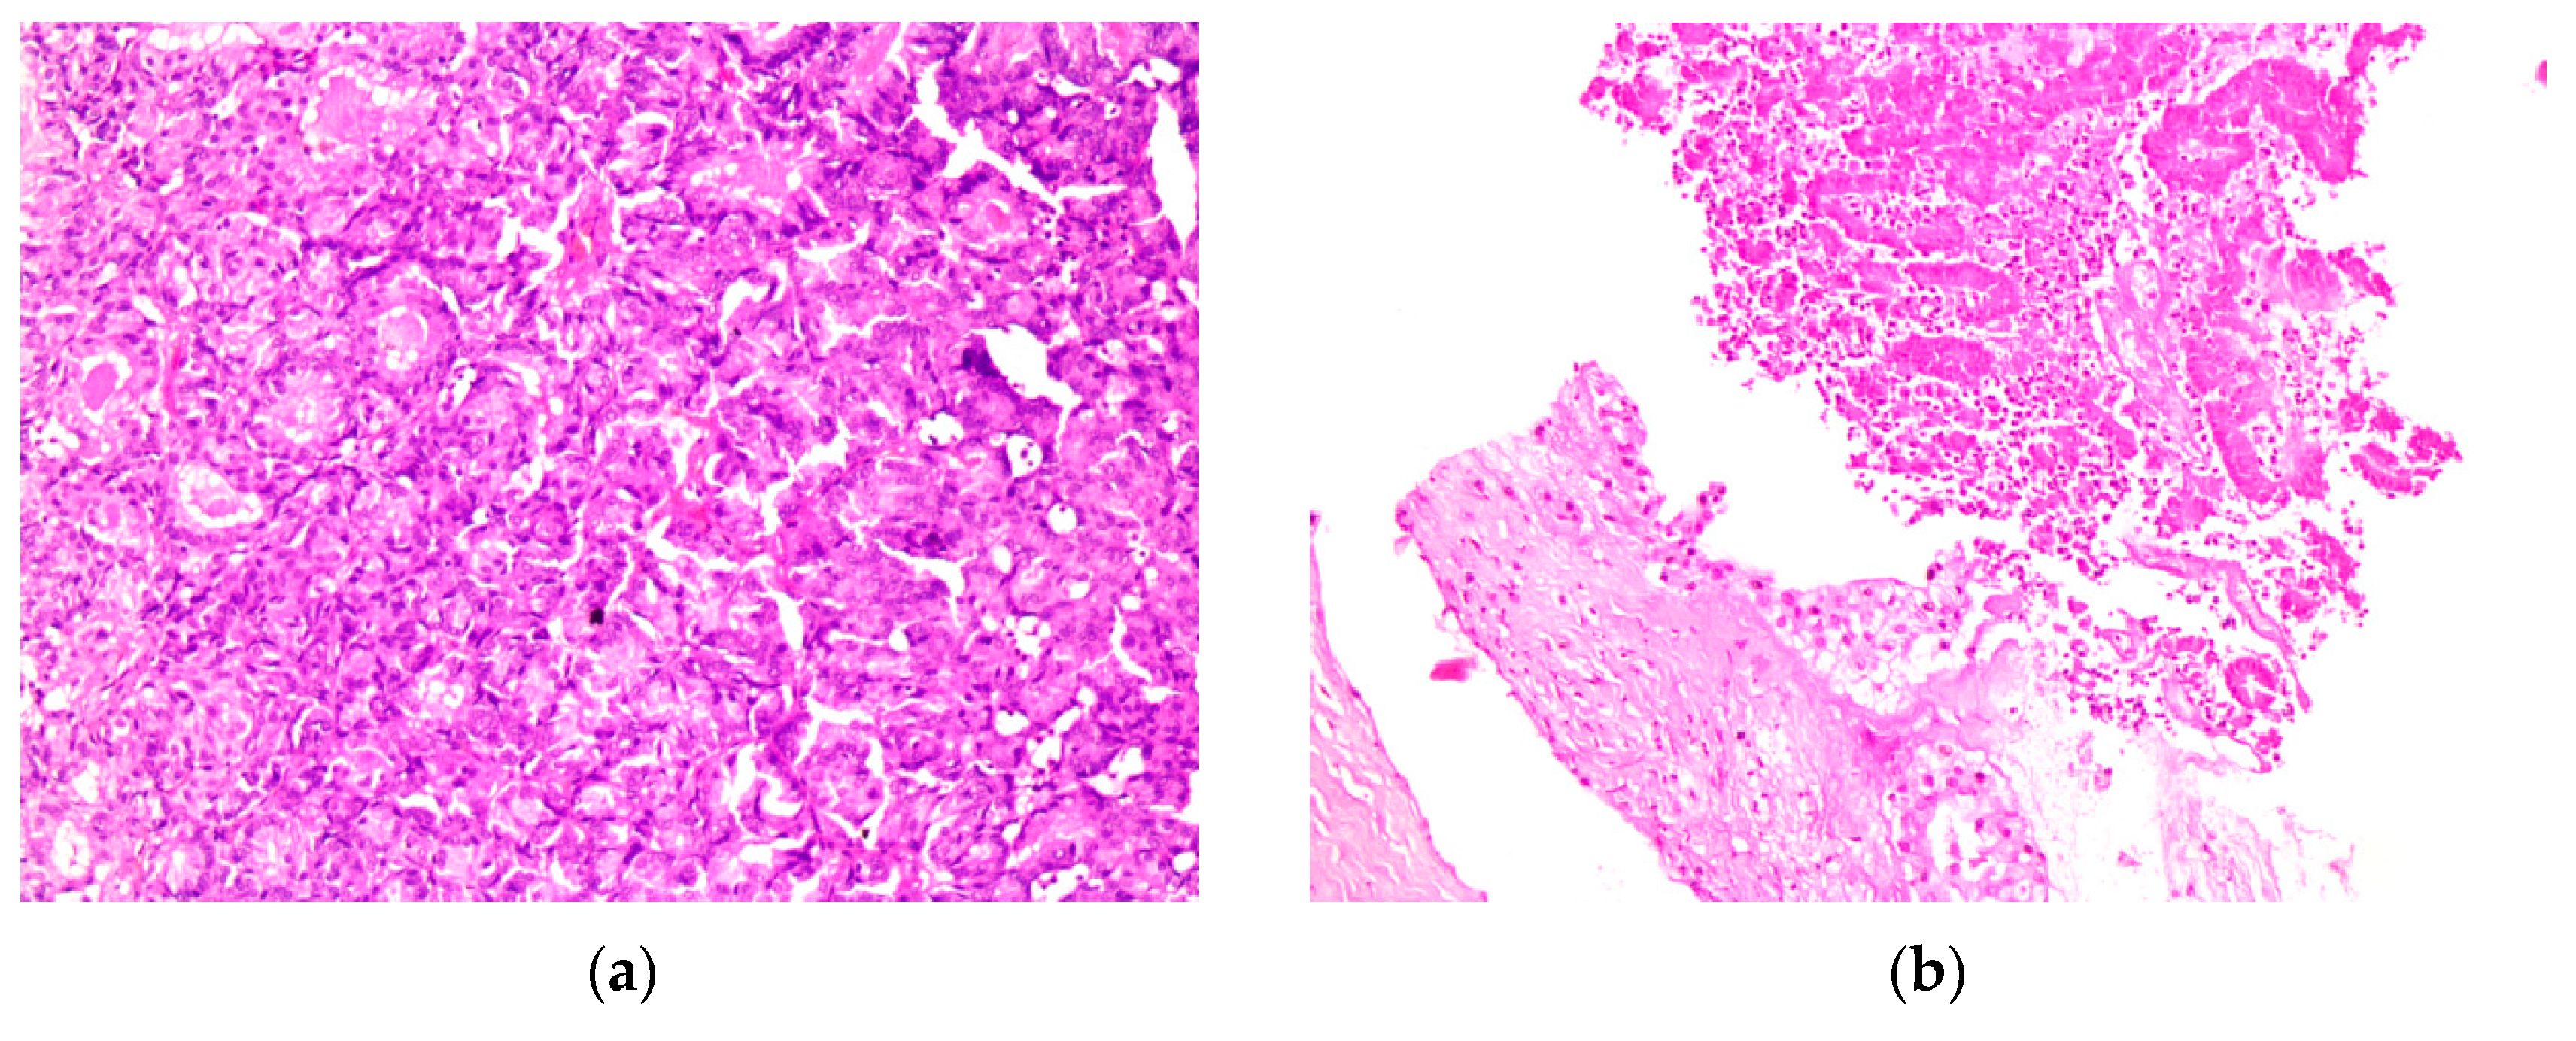

The histopathological findings (Figure 6) of a probe of the large chest and inguinal tumors show an endometroid adenocarcinoma, G2, with expression of cytokeratins MNF116 and CK7. The reaction to CK20, CDX2, Gata3, and TTFI was negative. The PAX8 marker was positive. The receptor status was positive to estrogen 90% and progesterone 40%. PDL1 was 1%. The intrinsic subtype was a microsatellite stabile tumor.

Figure 6.

(a) HE; 250× magnification under a microscope, metastasis of the rectus abdominis muscle; (b) HE 250× magnification under a microscope, invasion of the soft tissue from the endometrial cancer metastasis on the right thorax wall. Abbreviations: HE, hematoxylin -eosin.